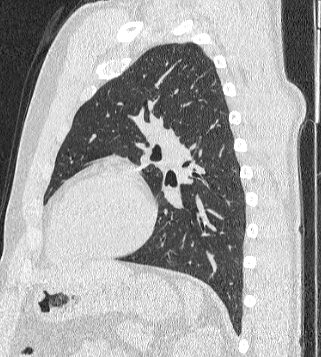

Компьютерная томография бронхов представляет собой виртуальную бронхоскопию, которая позволяет получить точную и достоверную информацию о состоянии трахеи, бронхов, а также оценить структуру легочной ткани, кровеносных сосудов, органов средостения. При обычной бронхоскопии эндоскопический зонд вводится внутрь через дыхательные пути и производится осмотр слизистой трахеи и бронхов, поэтому процедура относится к инвазивным и часто проводится под наркозом.

На основе данных, полученных при сканировании, аппарат создает наглядную 3D модель бронхиального дерева с высочайшей точностью и достоверностью, которая позволяет просматривать интересующие анатомические структуры в разных плоскостях. Метод обладает высокой точностью и дает возможность исследовать мелкие бронхи и бронхиолы, которые из-за узкого просвета бывает невозможно осмотреть при помощи эндоскопической бронхоскопии (возможности метода ограничены размером зонда).